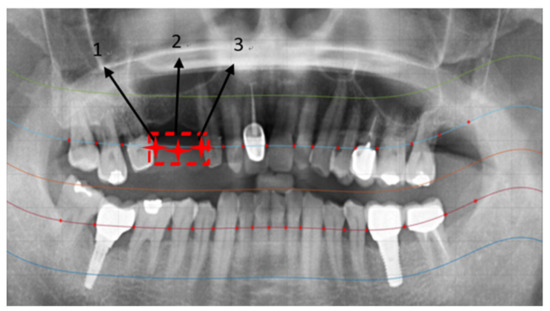

2.2.2. Curve Adjustment

2.2.3. Positioning Numbers